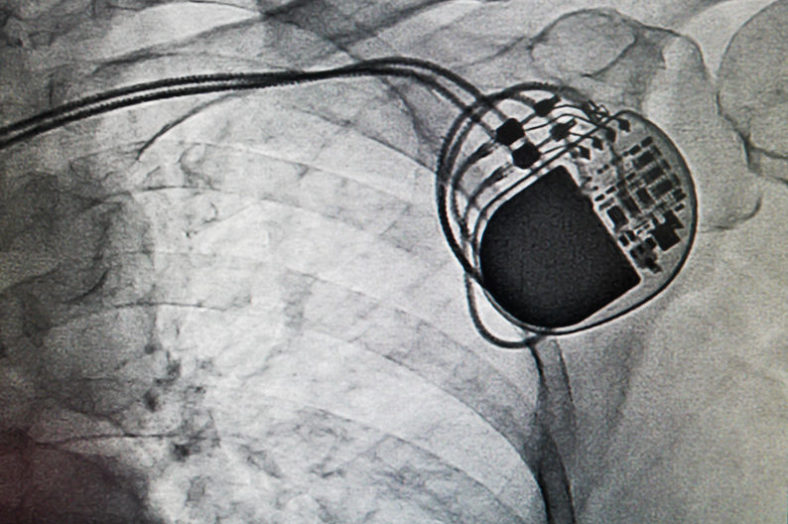

Shmedtronic Release New ICD-Pacemacer-WiFi Hotspot

ST. PAUL, MN – In response to patient feedback on how to make their ...